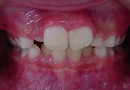

治療前 治療後

この様な歯並びの方はかなり見受けられるとと思われます。

当矯正歯科医院では、咬合バランスを改善する為には、

顎骨の拡大だけでは不十分と考ています。

その為、かみ合わせの高さなど立体的に改善していく事を心がけて日々治療しています。

今回も治療には、独自の方法とビムラー・t4k等を利用して改善しました。

今後、永久歯の歯並びは永久歯が萌えてから改善していく計画です。

顎骨のバランスは良好の為、永久歯を抜歯する必要は全くありません。